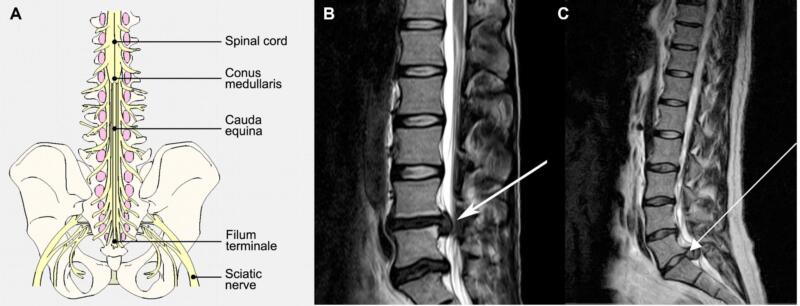

CES xảy ra do sự chèn ép các rễ thắt lưng cùng ở phía dưới L1 (hình 18), thường có biểu hiện yếu chi dưới không cân xứng, tê rần vùng đáy chậu (vùng S3-S5 chi phối), và rối loạn chức năng ruột/ bàng quang, cùng với đau lưng và rối loạn dáng đi. Cần lưu ý đánh giá tình trạng tê rần vùng đáy chậu, trương lực cơ trực tràng, và thể tích nước tiểu tồn dư sau khi tiểu tiện. Liên hệ giữa triệu chứng và hình ảnh học là rất quan trọng vì triệu chứng có thể xảy ra cấp tính hoặc mạn tính, và thời điểm xảy ra triệu chứng có ý nghĩa quan trọng trong quyết định phẫu thuật. CES cấp cứu xảy ra ở BN có khiếm khuyết thần kinh cấp tính hoặc tiến triển trong 1-2 ngày. Chèn ép do thoát vị đĩa đệm cấp, nhiễm trùng, và xuất huyết (tự phát hoặc sau mổ) là những khả năng có thể xảy ra. CES hiếm khi xảy ra, tỷ lệ 1:65 000 bệnh nhân và chỉ khoảng 1-2% BN thoát vị đĩa đệm. Cần phân biệt CES với hội chứng chóp tủy, là hội chứng xảy ra do chèn ép chóp tủy với biểu hiện yếu hai chi, tê rần đáy chậu, và rối loạn chức năng ruột. CES cũng có thể xảy ra do gãy đốt sống hoặc u.

Hình 18. Thoát vị đĩa đệm gây CES. A. Sơ đồ chùm đuôi ngự với chóp tủy ở ngang L1. B. Thoát vị đĩa đệm ở L4L5 hoặc C. L5S1 gây chèn ép chùm đuôi ngựa.